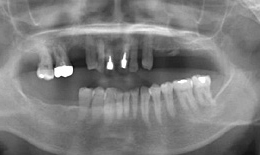

インプラント症例(23) 60歳 女性

- 保存困難な歯を抜歯後、インプラントを5本埋め込んで、セラミックスクラウンを被せた

- インプラントを2本埋め込んで、セラミックスクラウンを被せた

フィクスチャー 7本 |

285,000×7=1,995,000円(税抜) |

上部構造

(ハイブリッドクラウン)7本 |

135,000×7=945,000円(税抜) |

上顎前歯 メタルボンドクラウン |

97,000×6=582,000円(税抜) |